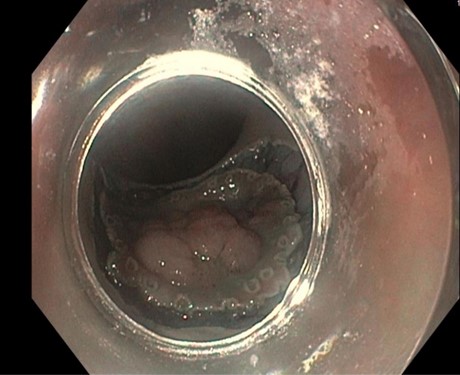

Eine Patientin stellte sich bei uns mit Beschwerden durch Gallensteine im Gallengang vor. Aufgrund der vorangegangenen Magenbypass-Operation war die Papille auf konventionellem endoskopischem Weg nicht erreichbar. Nach ausführlicher Aufklärung entschieden wir uns gemeinsam mit der Patientin für ein modernes, minimal-invasives Verfahren: die sogenannte EDGE-Prozedur (Endoscopic Ultrasound-Directed Transgastric ERCP).

Hierzu wurde zunächst mithilfe der Endosonographie (Ultraschall von innen) der ausgeschaltete Magenanteil aufgesucht. Dieser wurde gezielt punktiert und die korrekte Lage unter Röntgendurchleuchtung mit Kontrastmittel überprüft (Abbildung 1).